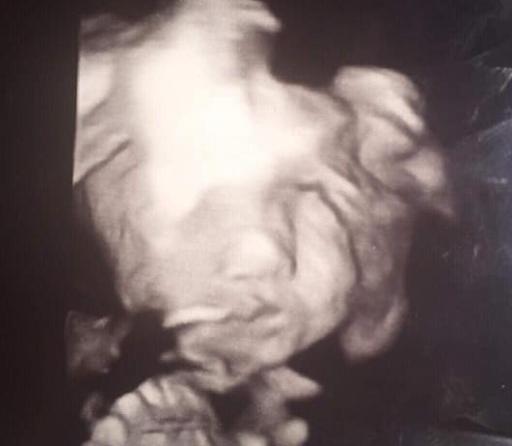

Con 24 semanas de gestación, a Iyanna le confirmaron que tendrá una nena, pero reaccionó con sorpresa al ver la carita de su hija, que según ella se parece "a la del diablo".

Lo que realmente pasó es que la nena apareció de frente en el ultrasonido, algo poco habitual ya que suelen estar de costado y pro eso la imagen se distorsionó un poco, haciéndola parecer a un demonio.

"Nunca había visto nada igual, pero amo mucho al bebé diablo", expresó ella. Como era de esperarse. Además, se confirmó que la beba está en perfecto estado de salud y creciendo correctamente.